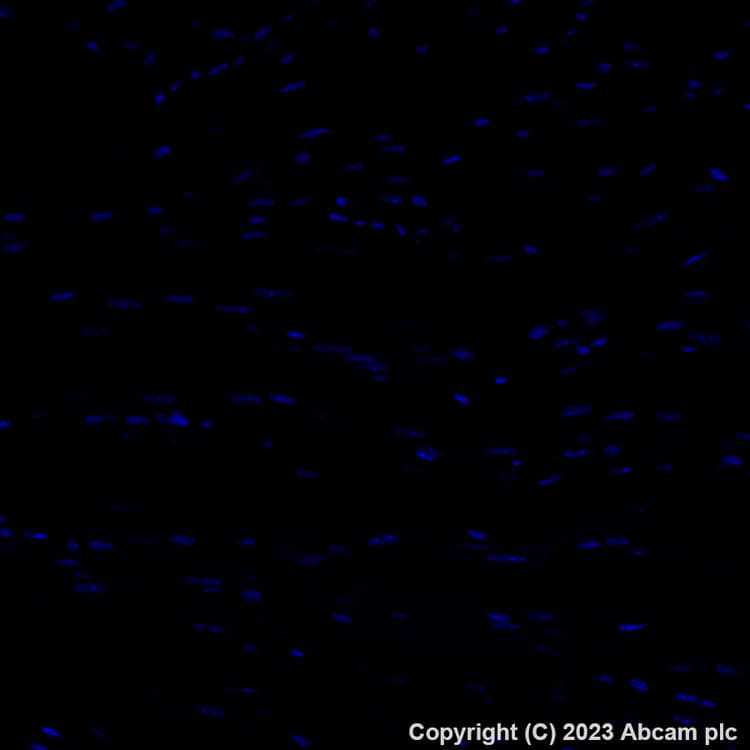

Alexa Fluor® 647 Anti-TIGIT antibody [EPR26037-152](ab308430)

Rabbit Recombinant Monoclonal TIGIT antibody - conjugated to Alexa Fluor® 647. Suitable for IHC-P and reacts with Mouse, Rat samples.

Applications IHC-P

Species Reactivity Mouse, Rat

Conjugation Alexa Fluor® 647